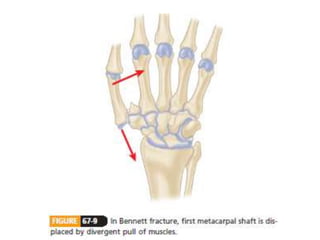

• #140 The distal metacarpal is adducted and supinated by the adductor pollicis. At the same time, the APL pulls the metacarpal radially and proximally.

Carpometacarpal (CMC) Fractures •The normal ROM at the thumb CMC joint • 50 degrees of flexion-extension • 40 degrees of abduction-adduction • 15 degrees of pronation-supination.